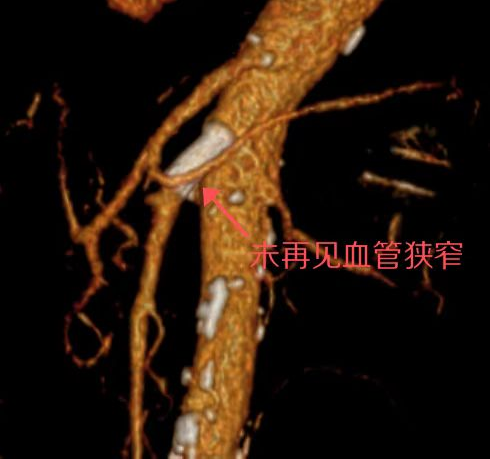

术后患者无明显腹痛,可正常饮食,可自行排气排便。术后复查肠系膜上动脉CTA提示支架通畅,肠系膜上动脉远端血供良好。